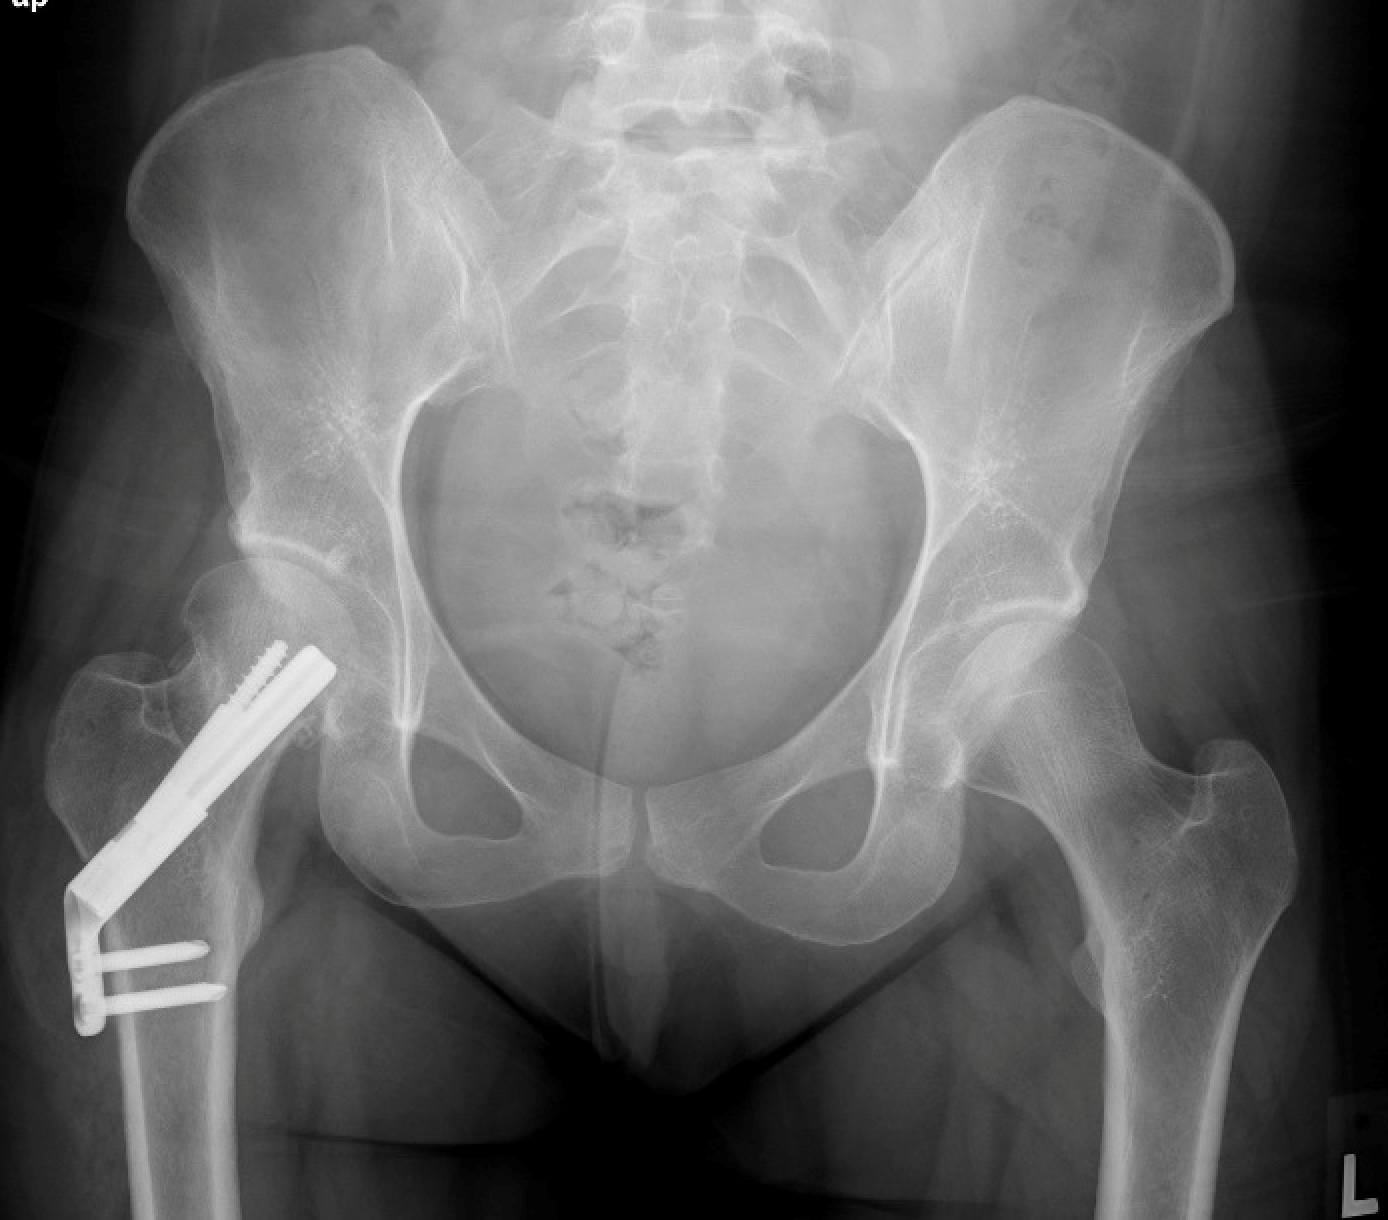

Intertrochanteric fractures are treated surgically with either a sliding compression hip screw and side plate or an intramedullary nail.

The compression hip screw is fixed to the outer side of the bone with bone screws. A large secondary screw (lag screw) is placed through the plate into the femoral head and neck. This design allows for compression at the fracture site, increasing stability and promoting healing.

hip fracture treated with compression screw and side plate

Two-part intertrochanteric fracture treated with a compression screw and side plate.

X-ray courtesy of Stuart J. Fischer, MD, FAAOS

The intramedullary nail is placed directly into the marrow canal of the bone through an opening made at the top of the greater trochanter. One or multiple screws are then placed through the nail and into the femoral head. An additional screw is placed into the bone to control rotation.

hip fracture treated with intramedullary nail

Two-part intertrochanteric fracture treated with an intramedullary nail.